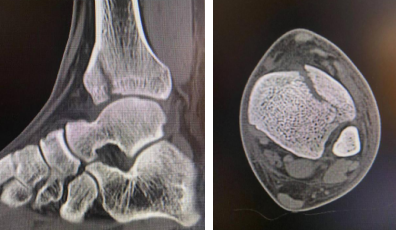

术前CT

术前MRI(左图),术中设计(右图)